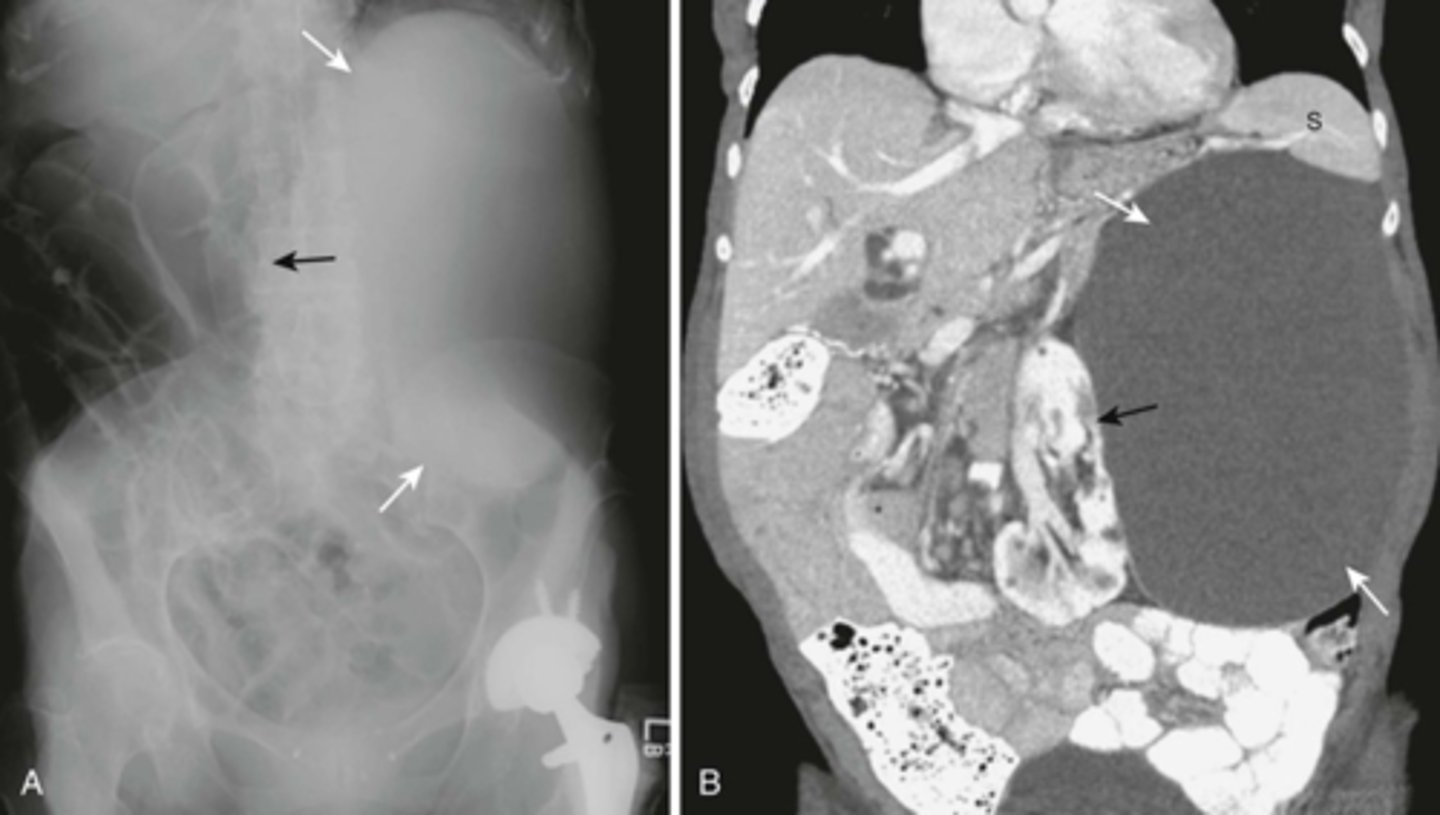

A:

WHITE ARROWS: soft tissue mass on LUQ

BLACK ARROW: displacement of bowels to the right

B: CT of the same patient

WHITE ARROW: large renal cyst arising from left kidney, displacing it and surrounding bowel.

BLACK ARROW: left kidney.

S: spleen, compressed by cyst.